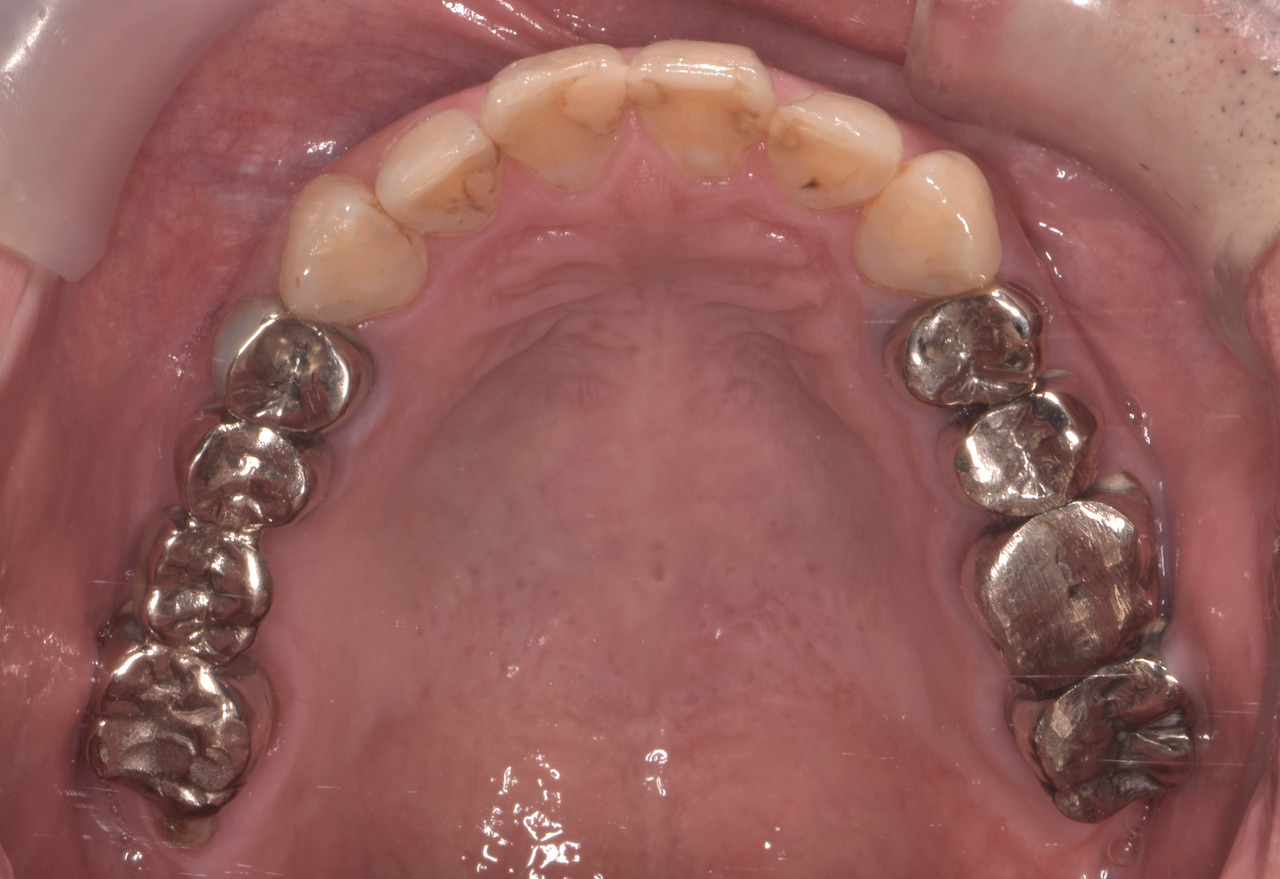

全顎的に複数の治療部位で、インプラント・ブリッジ・ダイレクトボンディング・セラミッククラウンなど、適切な治療方法を組み合わせて包括的な治療を進めました。